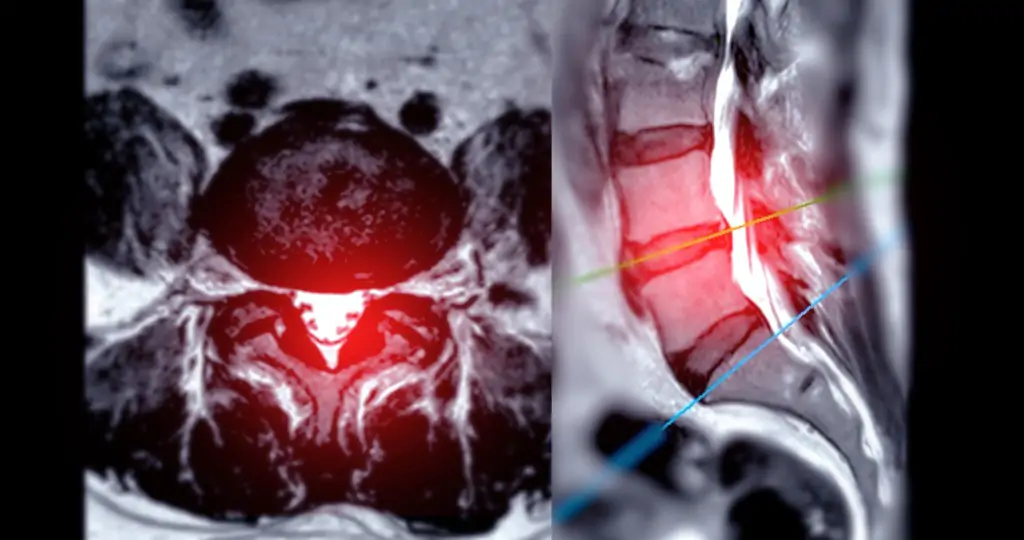

脊椎圧迫骨折の確定診断にはMRI検査が欠かせません。レントゲンでは新しい骨折と古い骨折の区別がつきにくく、ごく軽度の骨折は見落とされることもあります。当院では院内のMRI検査で骨折の状態を詳細に評価し、脊椎専門医が適切な治療方針を提案します。

MRI検査 レントゲンでは見つからない微小な圧迫骨折も検出でき、骨折の新旧(急性・陳旧性)の区別も可能です。神経への影響の評価にも有効です。